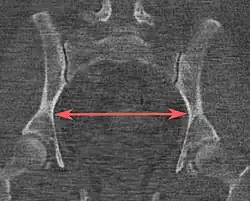

| Interspinous distance |

![]() Axial plane |

The line between the closest bone points of the ischial spines | 9.5 to 11.5 cm.[6] | |